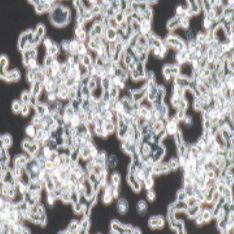

半贴壁半悬浮

2) 形态:半贴壁半悬浮